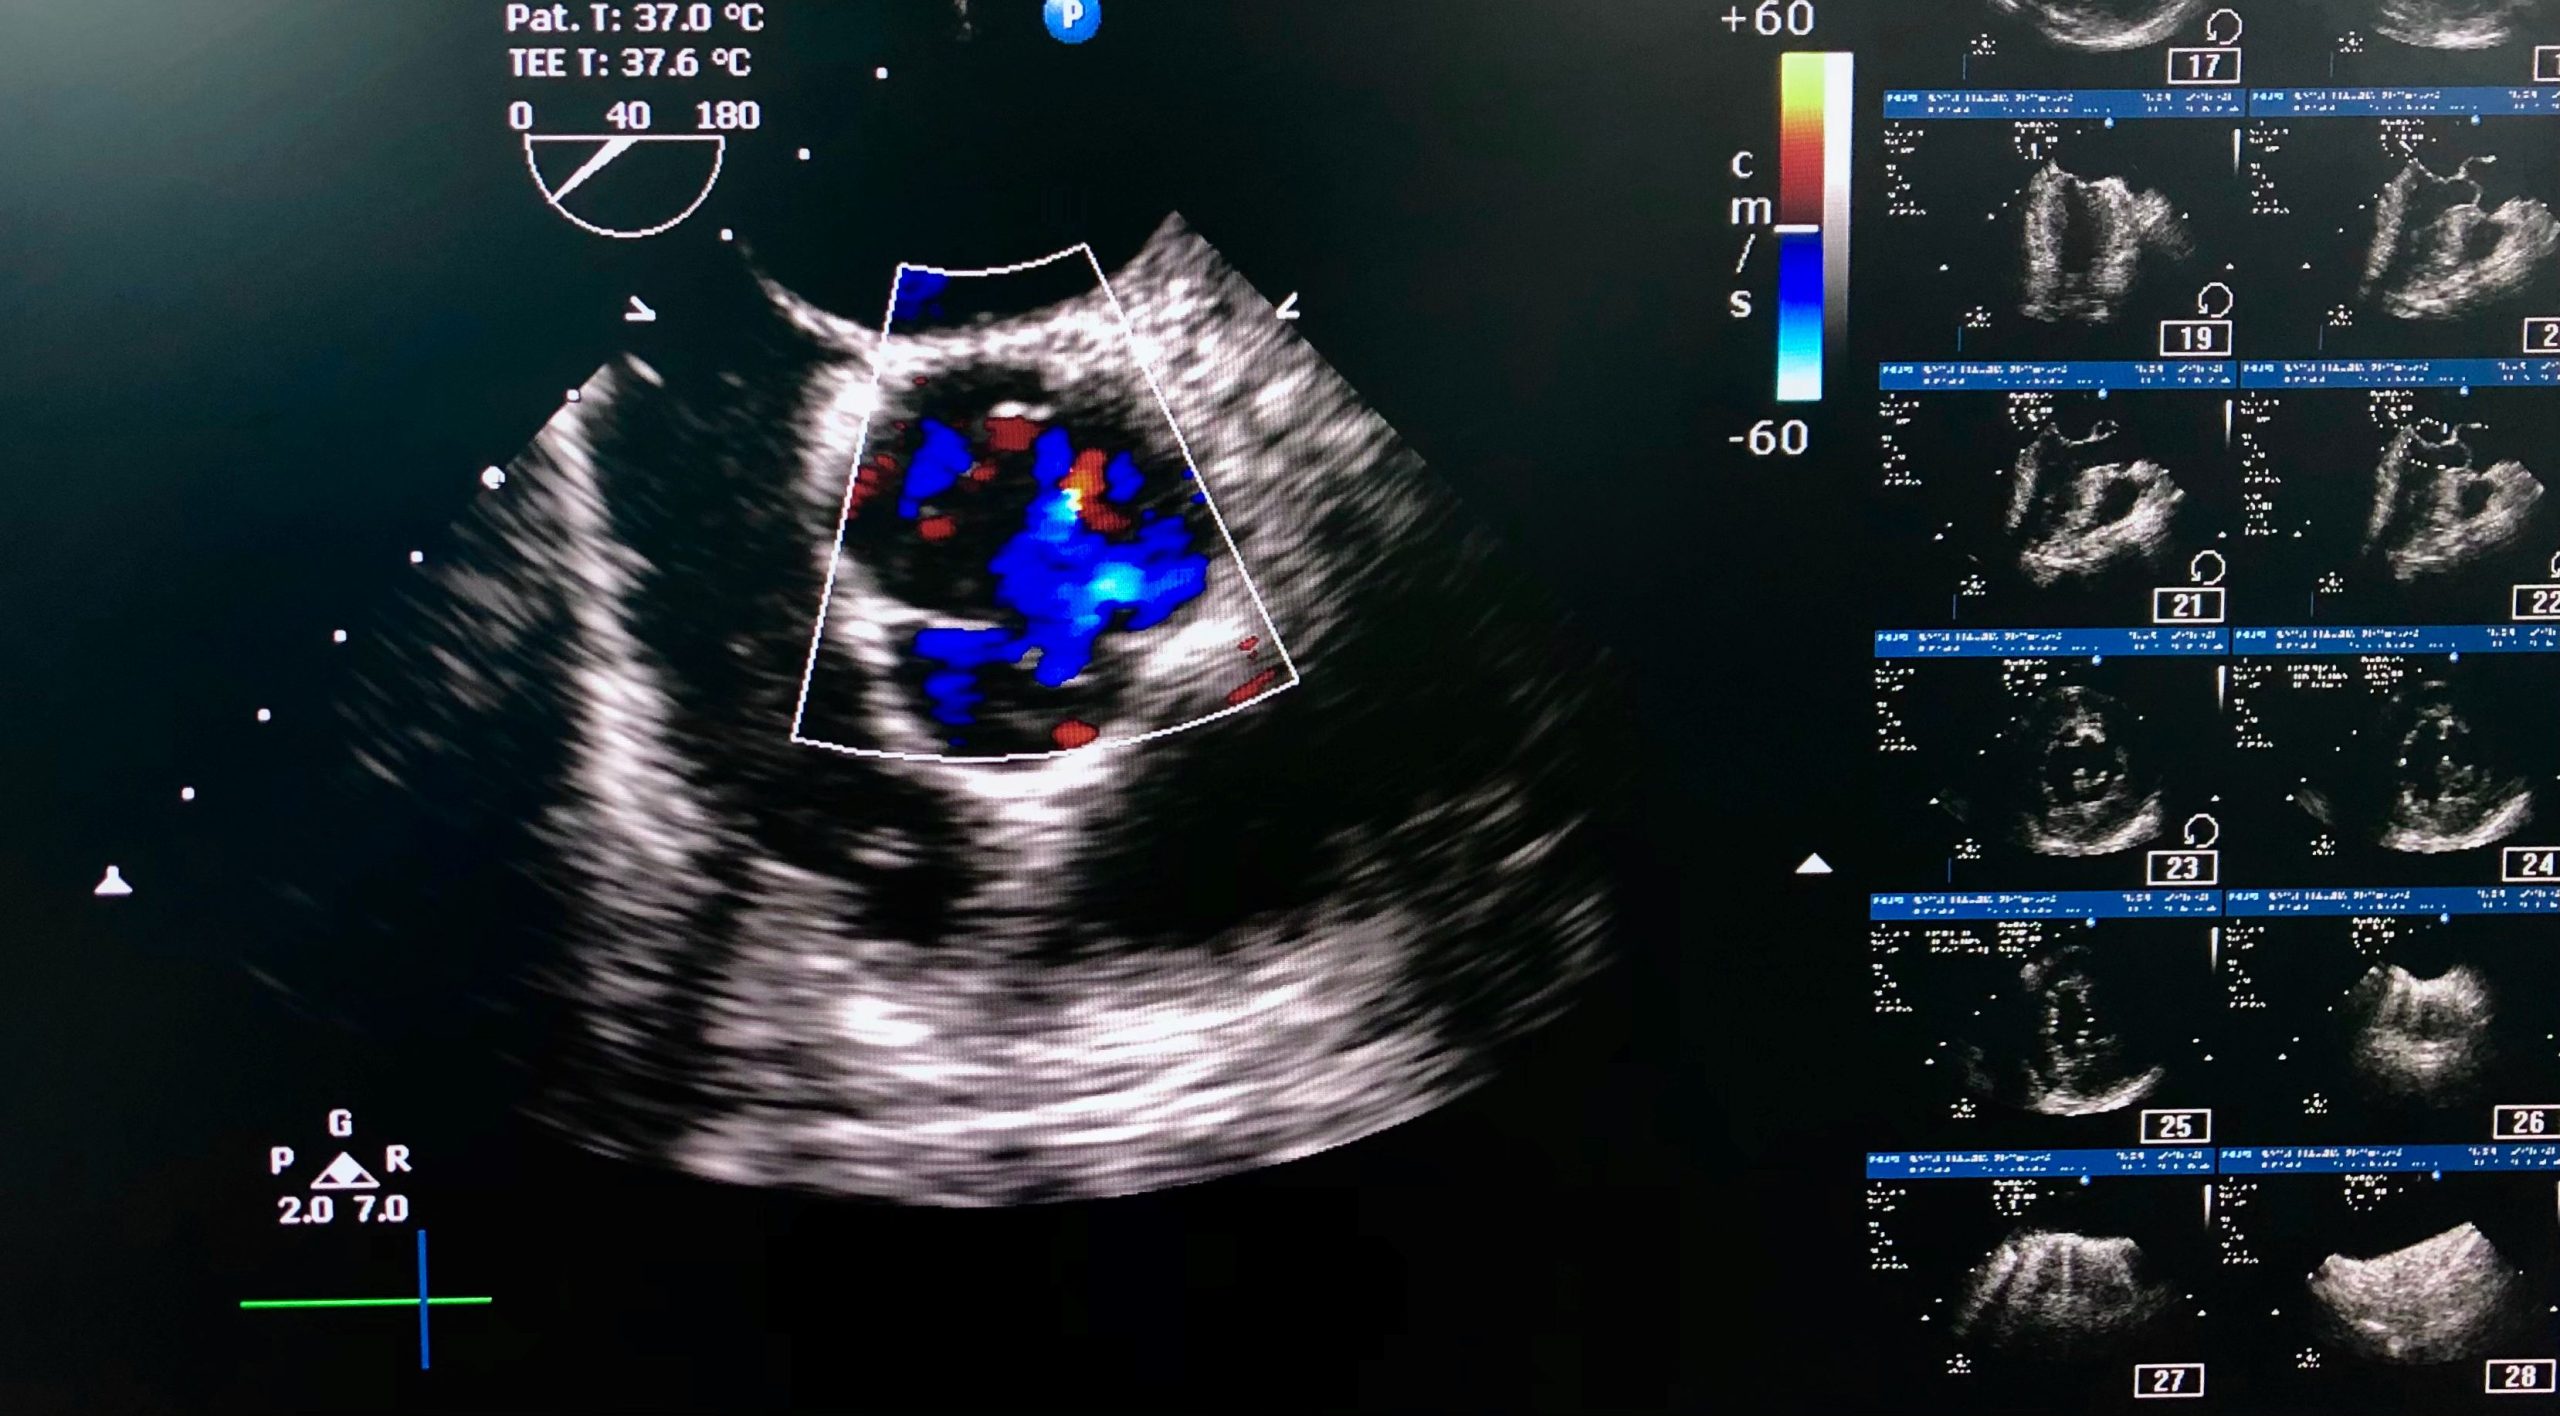

A transesophageal echocardiogram (TEE) uses ultrasound to capture detailed images of the heart from inside the body, unlike a standard echocardiogram performed on the chest. TEE is often used during surgery to guide the procedure and immediately assess heart function.

“The cardiac anesthesiology team collaborates closely with our cardiac surgeons and cardiologists to acquire and interpret real-time transesophageal echocardiographic images throughout surgery,” he said. “This advanced imaging allows us to identify structural or functional issues that may not have been visible before the procedure, assess how well the heart responds and confirm everything is working properly before we finish. If we detect any problems, such as valve issues or blood flow concerns, we can address them immediately, reducing the risk of complications and supporting better long-term outcomes for our patients.”